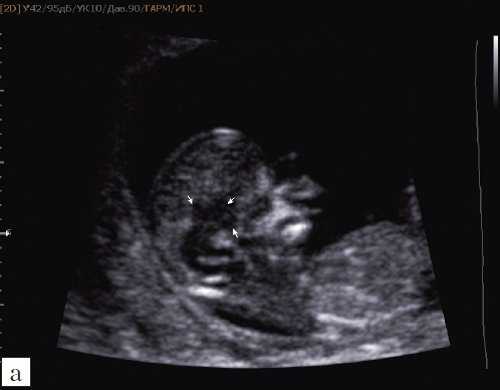

В аксиальном срезе головки привлекает к себе внимания то, что сосудистые сплетения расположены ближе к затылочной кости, чем к лобным костям. Расстояние между лобными костями и передним контуром сосудистых сплетений увеличено (указано стрелками)

В аксиальном срезе головки четверохолмие (обведено пунктиром) также расположено ближе к затылочным костям. Ножки мозга удлинены. 1-ножки мозга. 2-таламусы

При изучении стандартных ультразвуковых сканов (рис. 6-8) было подтверждено наличие синдрома Арнольда-Киари, вентрикуломегалии, открытой расщелины позвоночника - рахисхиза без кистозного компонента в поясничном отделе у плода в 12,4 недель беременности.

Рис. 6. Проявление синдрома Арнольда-Киари - смещение мозжечка, признак "банана" у плода со spina bifida, беременность 12,4 недель.